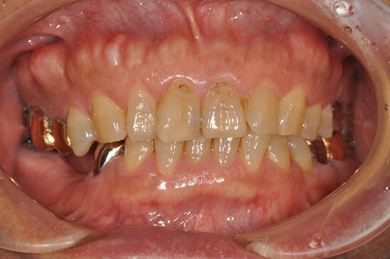

インプラント治療+セラミック治療

| 性別/年齢 | 男性 / 58歳 | ||||||||||||||||||||||||||||||||

| 主訴 | 部分入れ歯のバーが舌に当たるため、奥歯2本のインプラント治療を希望。 | ||||||||||||||||||||||||||||||||

| 治療方針 | 右下欠損部分をインプラント治療にて、機能的・審美的回復を行う。 | ||||||||||||||||||||||||||||||||

| 治療内容 | インプラント2本、メタルボンドセラミッククラウン8本、メタルボンドセラミック用土台6本 | ||||||||||||||||||||||||||||||||

| 総治療費 | 1,474,620円 | ||||||||||||||||||||||||||||||||

| 治療期間 | 1年6ヶ月 |